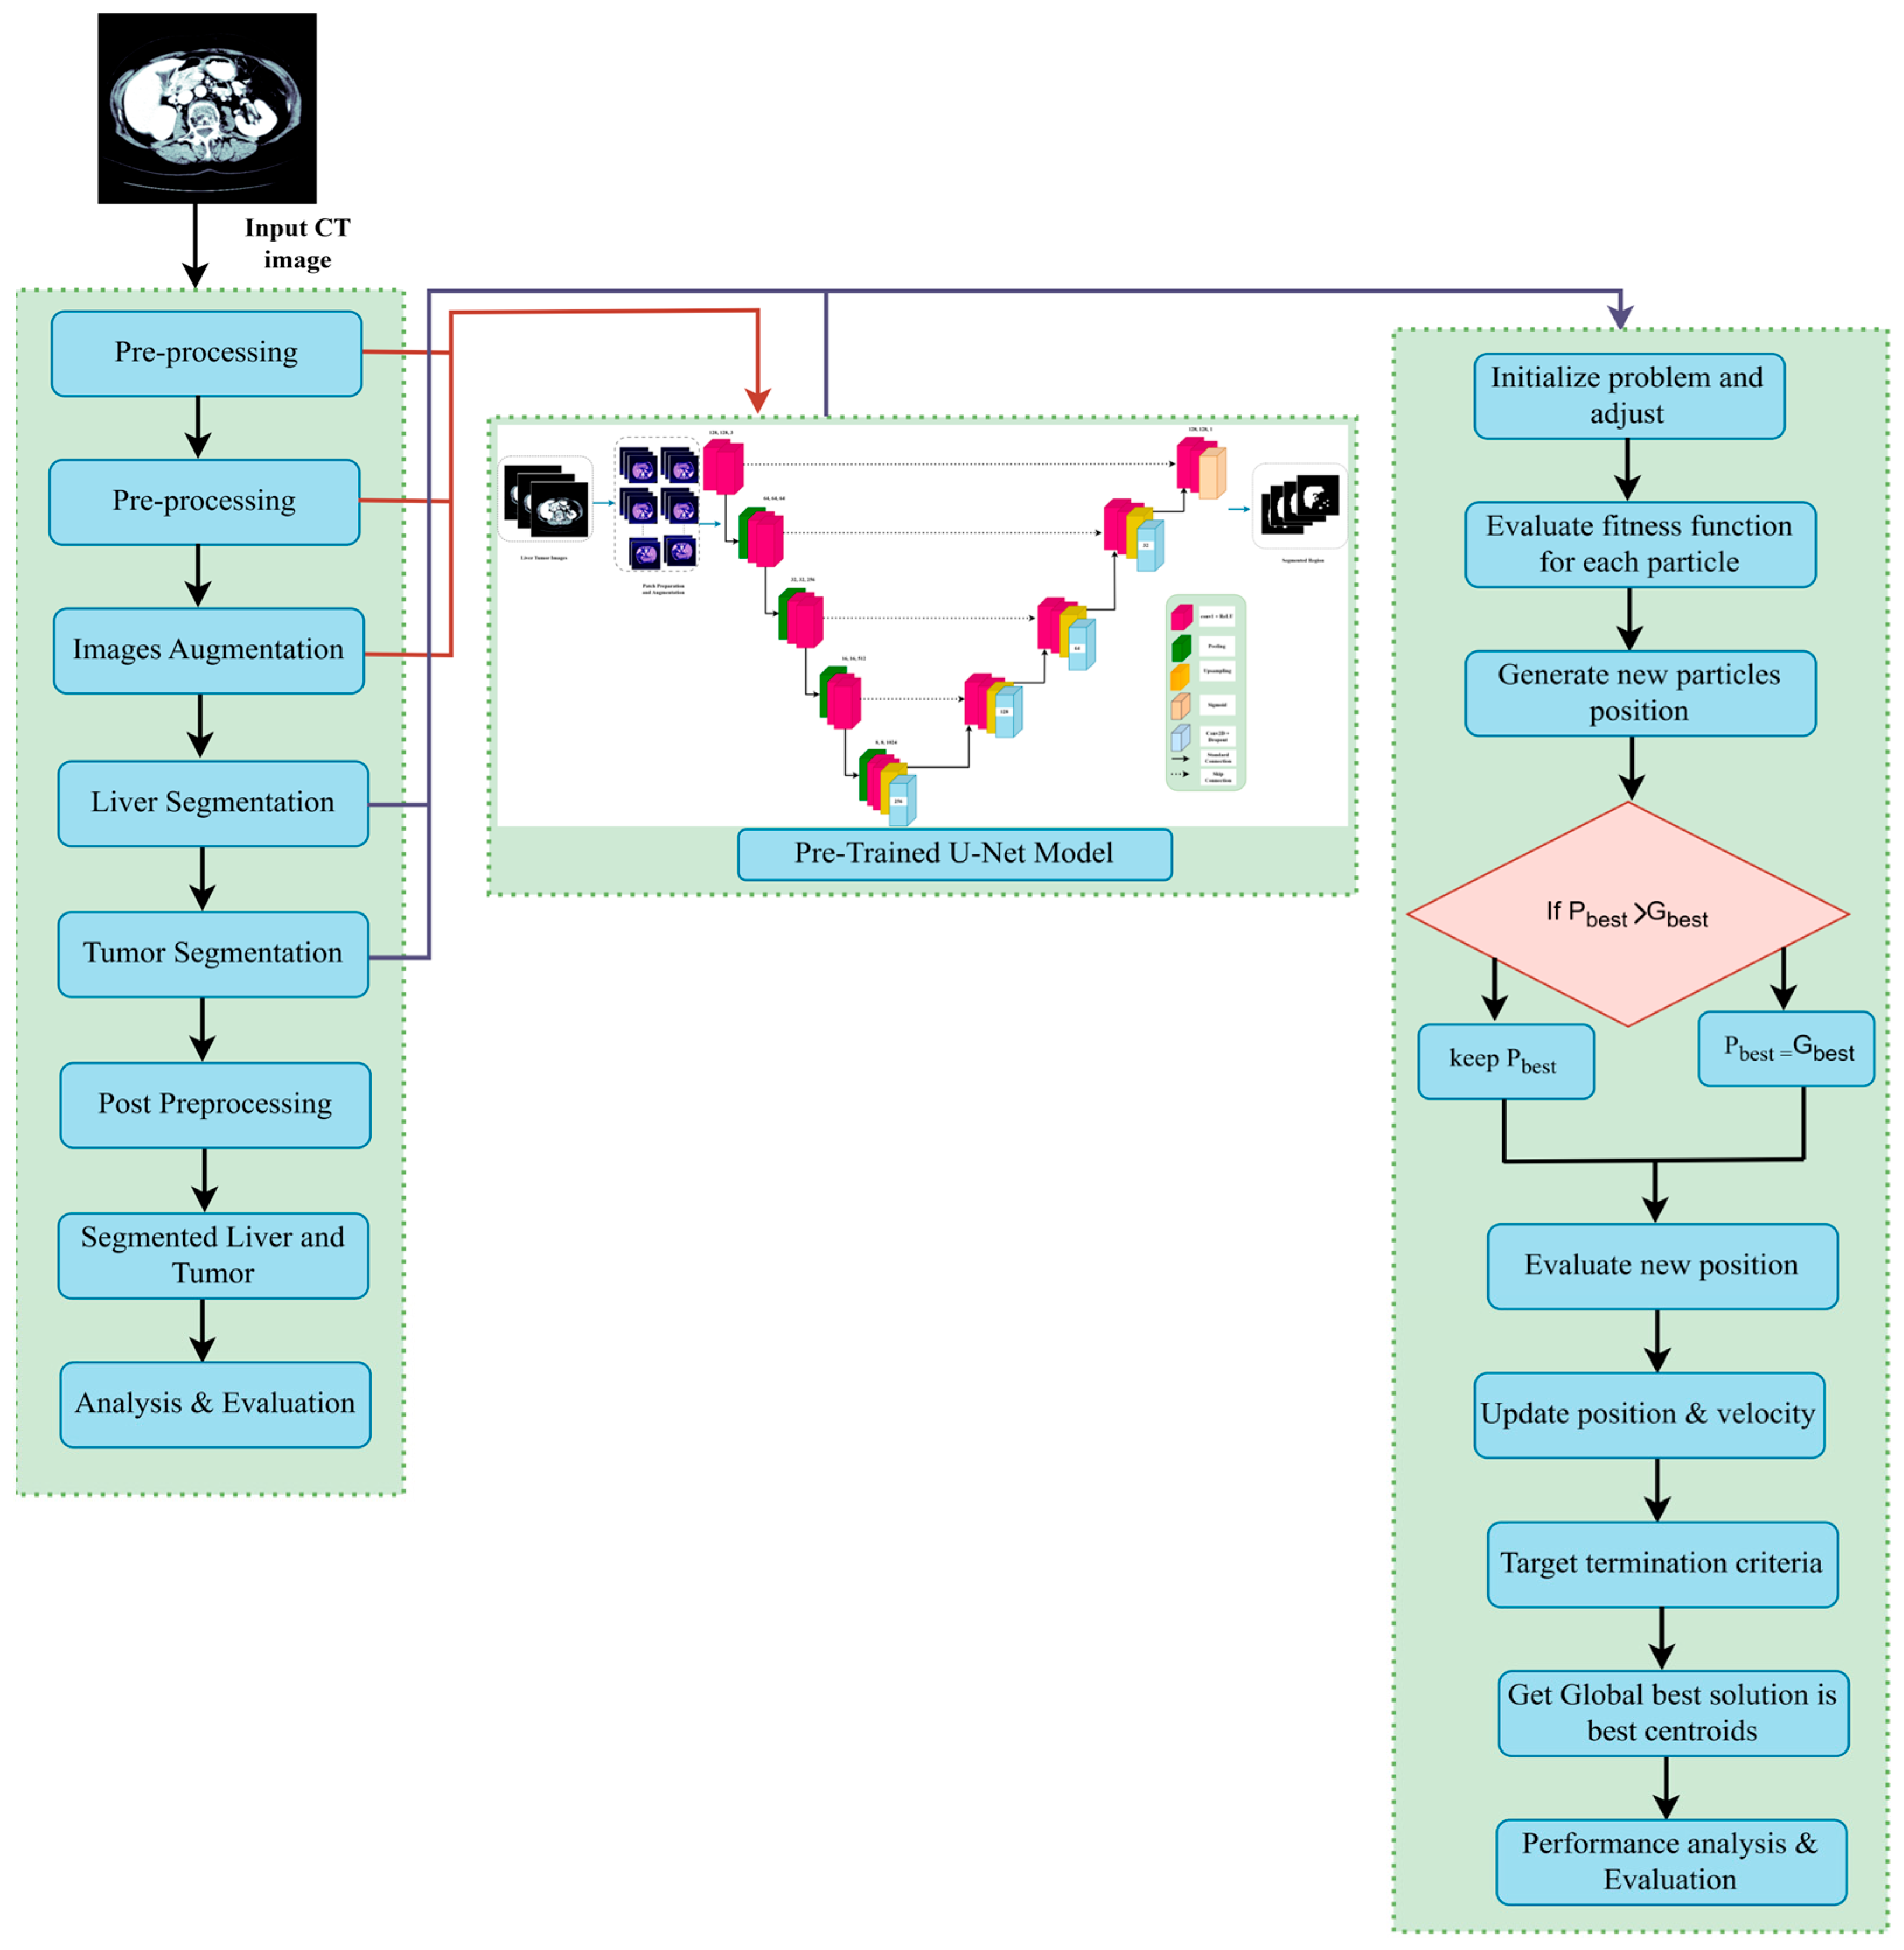

- We propose a novel hybrid optimization-segmentation framework called LiTs-Res-Unet + WOA, which integrates the Whale Optimization Algorithm (WOA) with a UNet-based architecture to automatically and adaptively tune the hyperparameters required for liver and tumor segmentation.

- Unlike prior studies that apply WOA to optimize a single parameter, we propose a closed-loop optimization framework in which WOA tunes a set of interdependent hyperparameters (learning rate, dropout rate, batch size) dynamically during training. This introduces a meta-optimization layer that is adaptive to the changing loss landscape of the ResNet-50–U-Net model.

- The inner level updates the network weights using backpropagation, and the outer level optimizes a population-based hyperparameter search using WOA by the validation Dice score. The convergence of validation performance shows that the hyperparameter optimization (HO) by the WOA outperforms the grid search and the Bayesian optimization methods because it achieves a better exploration–exploitation trade-off.

3. Methodology

3.2. Dataset Preprocessing

3.3. Based Model Architecture

3.3.1. Pre-Trained Encoder

3.3.2. Model Decoder Path

3.4. Swarm-Based Whale Optimization Algorithm (WOA)

3.5. Proposed U-Net Segmentation with WOA

3.5.1. Hyperparameter Tuning with Whale Optimization Algorithm

3.6. ResNet-50 + U-Net